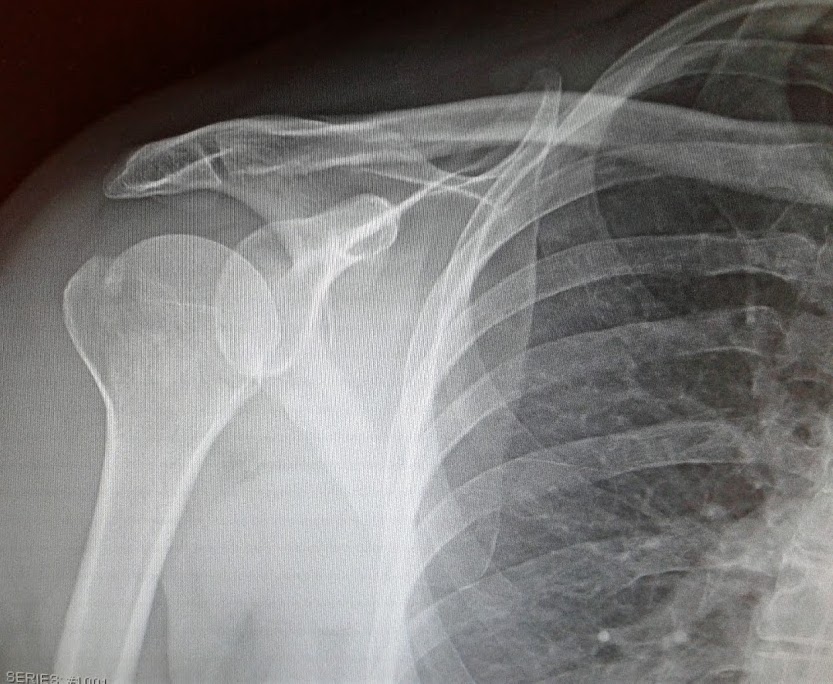

This is a photo of an x-ray of my broken right shoulder in 2017. (Minnesota Prairie Roots copyrighted file photo May 2017)

Bear with me. I also have an implant in my left wrist, the result of a 2018 fall which shattered my wrist. Ten screws hold that wrist plate in place. When the weather changes, I notice discomfort in my wrist. Likewise in my right shoulder. I broke that in 2017 after missing the last step on a hospital stairway while on my way to donate blood.